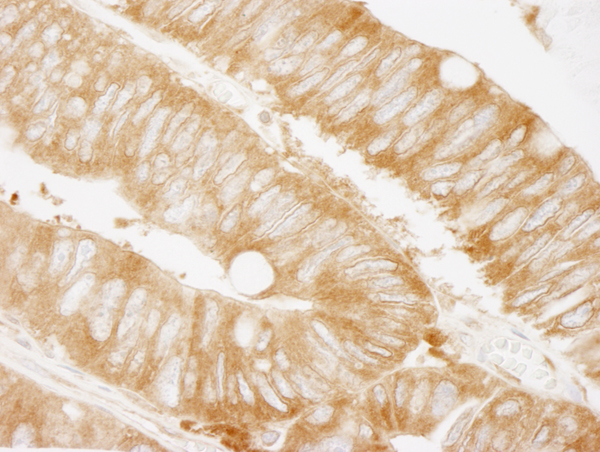

IHC (Immunohistochemistry)

(Detection of human KARS by immunohistochemistry. Sample: FFPE section of human colon carcinoma. Antibody: Affinity purified rabbit anti-KARS (Cat. No. AAA214042) used at a dilution of 1:250. Detection: DAB)